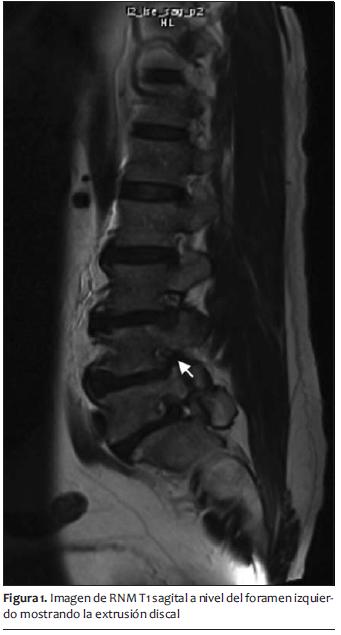

Resonancia magnética nuclear (RMN): extrusión discal paramediana izquierda en L3-L4 y en L4-L5 con compromiso del neuroforamen izquierdo, canal raquídeo estrecho en L3-L4, L4-L5. Espondilolistesis grado1 de L5 sobre S1. Artrosis facetaria lumbar baja (figuras 1 y 2).